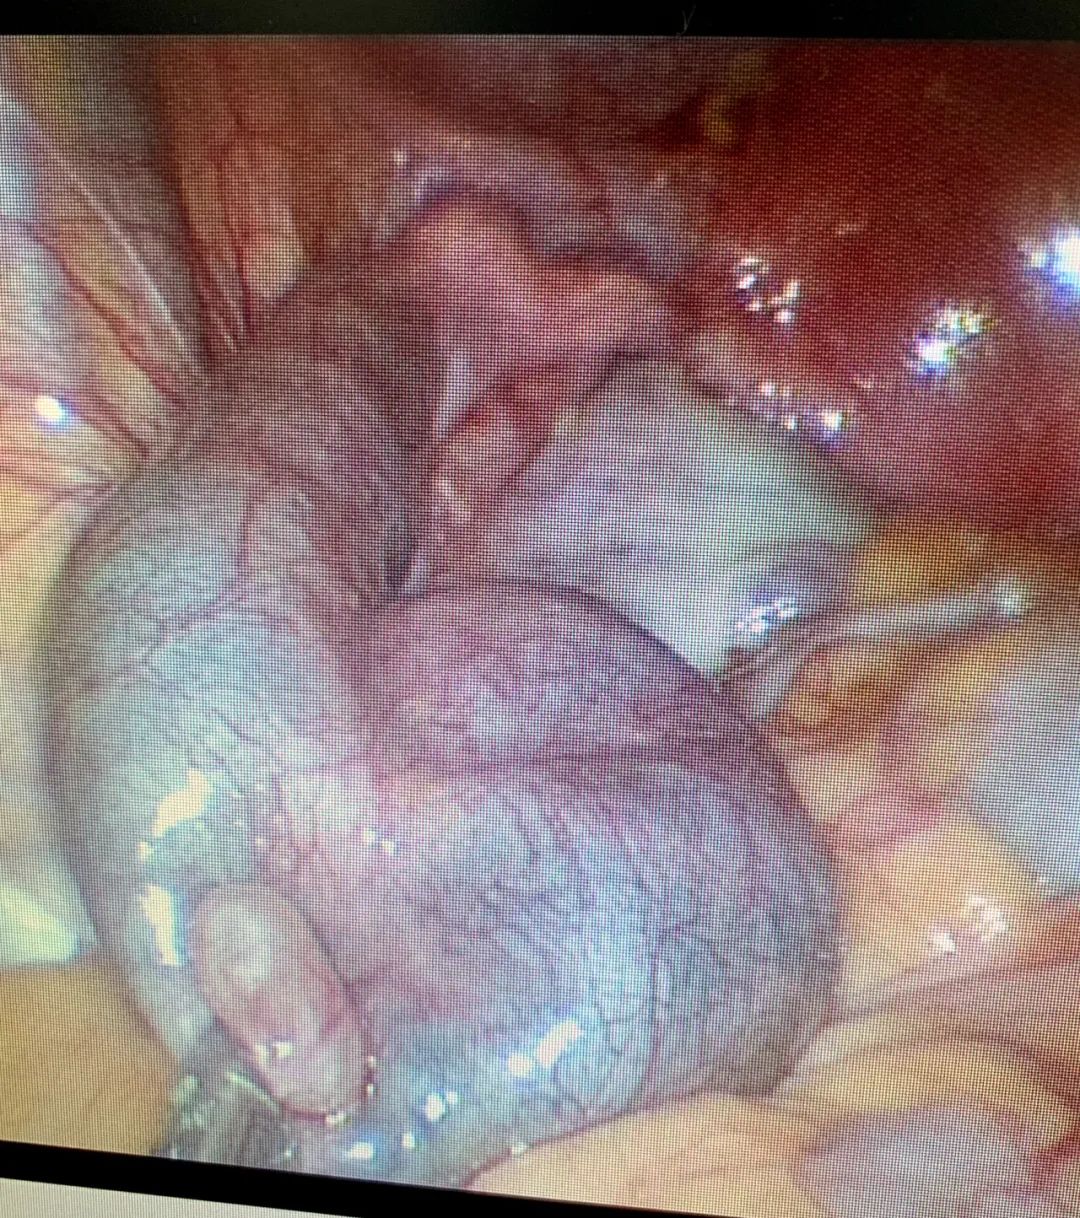

经讲解,蕾蕾接受了微创手术建议。昨天下午我们为其实施单孔腹腔镜手术,术中见双侧输卵管重度扩张、积水明显,呈现腊肠样、袋状,末端盲端、不见伞粘膜。如此严重的输卵管病变,不处理,永无怀孕可能。

LAP:双侧输卵管重度扩张、积水